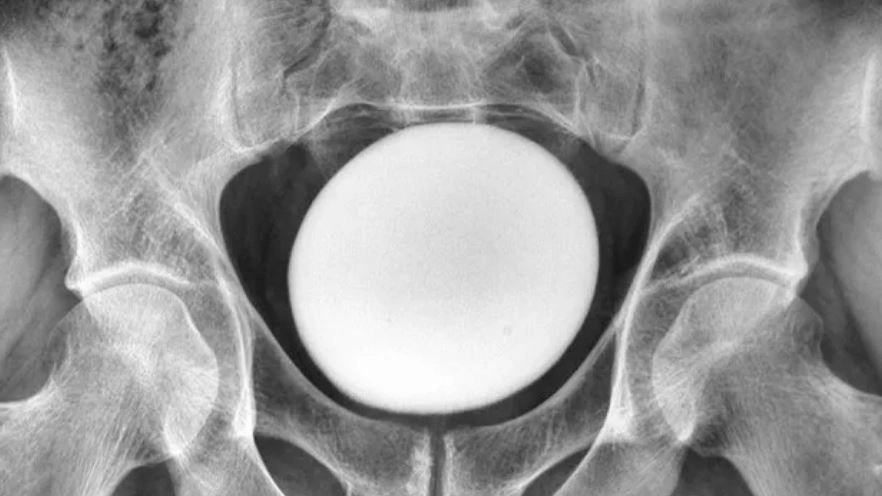

이란의 한 남성이 방광 불편함으로 병원을 찾았다가 예상 밖으로 타조알 크기의 거대한 결석을 발견해 제거 수술을 받았다.

의사들이 복부를 진찰하자 치골 위쪽에서 크고 매끄러우며 단단한 덩어리가 만져졌다.

이 덩어리는 골반이나 복벽에 붙어있지 않았다. 초음파 검사 결과 지름 약 11㎝의 달걀 모양 물체였다.

의료진은 이를 비정상적으로 큰 방광 결석으로 진단했다. 결석은 소변 속 미네랄이 결정으로 쌓이면서 자라는데, 약 85%가 칼슘으로 이뤄져 있다.

꺼낸 결석은 무게 826g, 길이 약 13㎝, 너비 약 10㎝, 높이 약 8㎝였다.